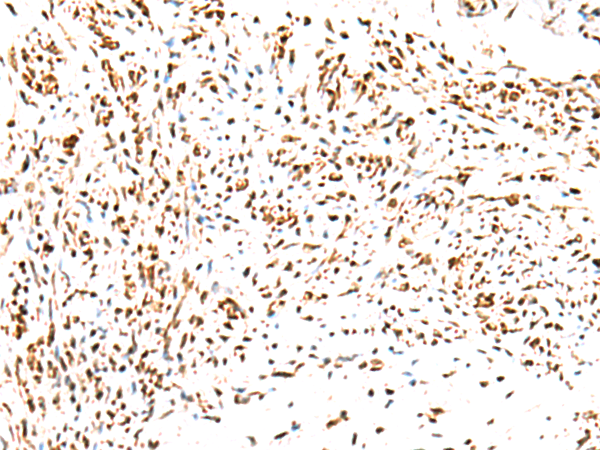

The image is immunohistochemistry of paraffin-embedded Human lung cancer tissue using P03095(KCTD13 Antibody) at dilution 1/50. (Original magnification: ×200) |

The image is immunohistochemistry of paraffin-embedded Human cervical cancer tissue using P03095(KCTD13 Antibody) at dilution 1/50. (Original magnification: ×200) |